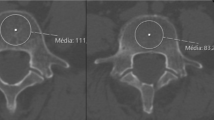

BMD

Six studies evaluated the magnitude of BMD in patients with and without adverse events [34, 46, 48,49,50, 53], of which four were of moderate quality, whereas the remaining studies were of high quality [48, 53]. Two of these studies also accounted for osteoporosis (T-score < − 2.5) [34, 48]; Cho et al. [34] included 86 patients and reported that the cage subsidence rates after LIF were significantly higher for osteoporotic patients than for non-osteoporotic patients (65.4% and 17.6%, respectively; p < 0.001). Park et al. [48] found that the adverse event rates of cage migration cases and combined cage subsidence and migration cases were 9.7% and 18.1% for osteoporotic patients (72), respectively, whereas the rates were 2.6% and 4.6% for all patients (n = 784) in the study. Yao et al. [53] evaluated 126 cages used for LIF, the mean T-score for 43 cages with subsidence was − 1.8, whereas that for 83 cages without subsidence was − 1.1. Singhatanadgige et al. [49] included 135 cages used for TLIF, the mean T-score for 80 cages with subsidence was − 1.3, whereas that for 55 cages without subsidence was − 1.1. Tempel et al. [50] evaluated 80 patients with LIF, wherein 39 (48.8%) had decreased BMD (T-score < − 1), and for 23 patients with cage subsidence, 18 (78.3%) had decreased BMD. Okuyama et al. [46] evaluated 52 patients with LIF, with a mean BMD of 0.879 g/cm2. For 12 patients with non-union or undetermined union, the mean BMD was 0.674 g/cm2 and 0.710 g/cm2, respectively. The findings of these studies identified a trend of higher subsidence rates in patients with decreased BMD and osteoporosis. In addition, one study with moderate quality mentioned patients with cage subsidence had significantly low Hounsfield unit (HU) of their CT scans (113.4 ± 10.5, p = 0.0075) [45], and low HU of CT scans was associated with low BMD. Xi et al. [52] held the same point in their study because the mean HU of patients who experienced cage subsidence was 20.8% lower than the mean HU of patients without cage subsidence.